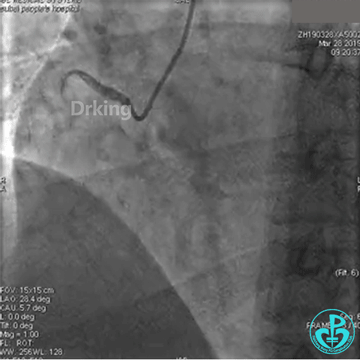

以下是导丝成功通过严重扭曲病变的图:

把Sion导丝送至高位OM的远段,在双腔微导管的辅助支撑下,把BMW导丝通过LCX扭曲及病变处顺利送至远段,撤出双腔微导管,2.0×20mm球囊对病变处PTCA后狭窄减轻,于病变处植入2.75×23mm支架一枚,后分别用2.75×12mm、3.0×12mm球囊对支架内后扩,复查造影原病变处狭窄消失,TIMI血流三级。